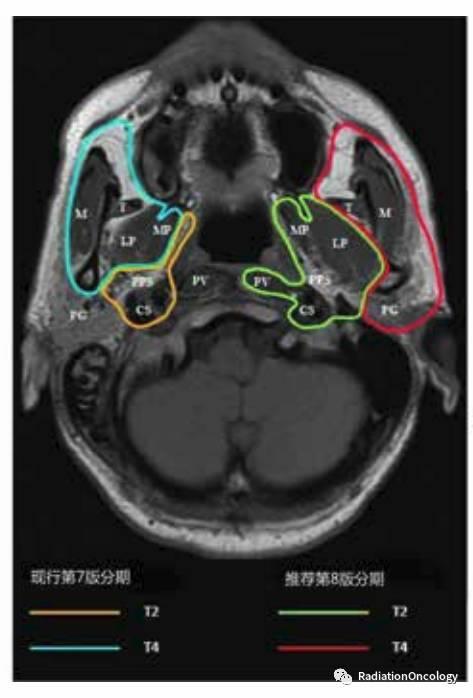

鼻咽癌4种分期的咀嚼肌间隙

图片尺寸473x698